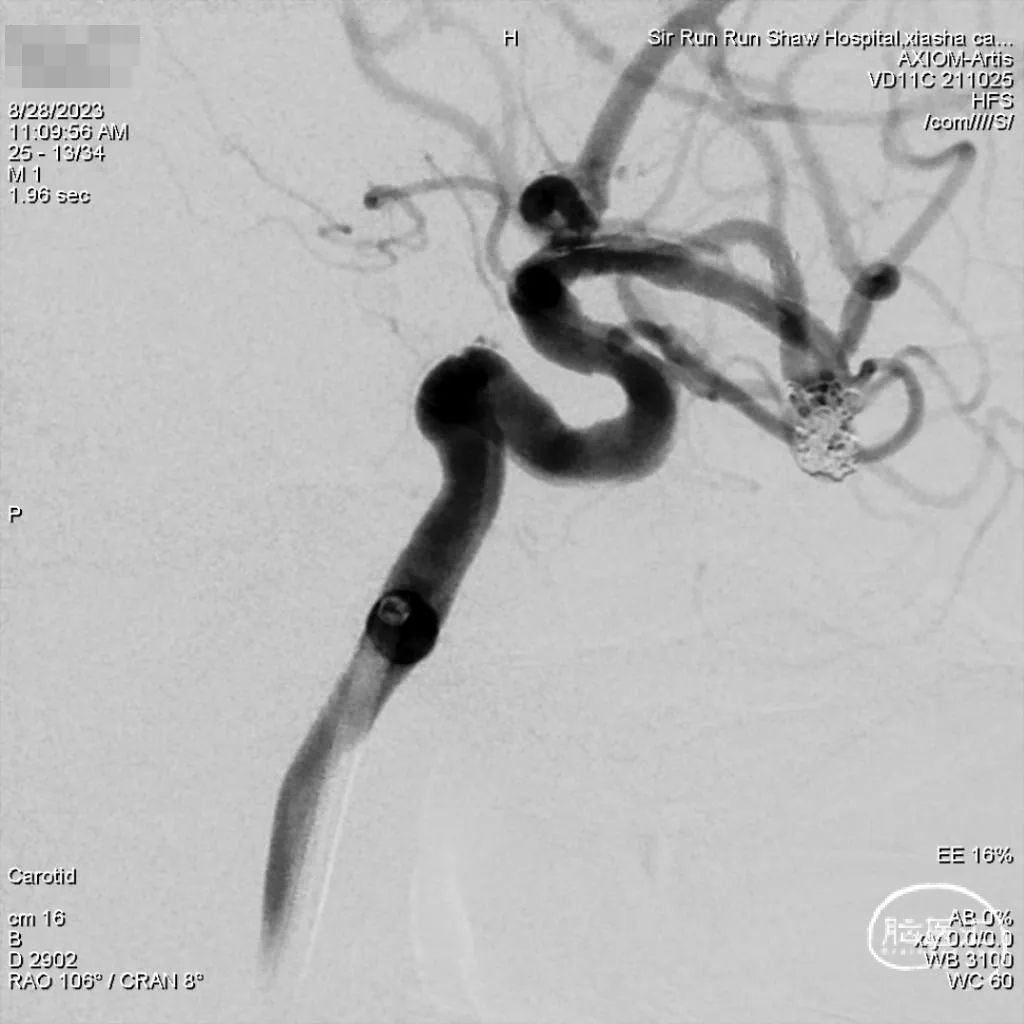

脑血管造影(2023-07-18):II型弓;右侧大脑中动脉动脉瘤。

术前诊断:右侧大脑脚梗死,右侧中动脉M1分叉部动脉瘤。

动脉瘤尺寸:最大直径8.6mm,瘤宽5.9mm,瘤颈直径4.2mm。

3D重建后,选择栓塞工作角度。

工作位造影。

术后即刻影像:术后双容积重建,见瘤体栓塞理想,支架位置合适。